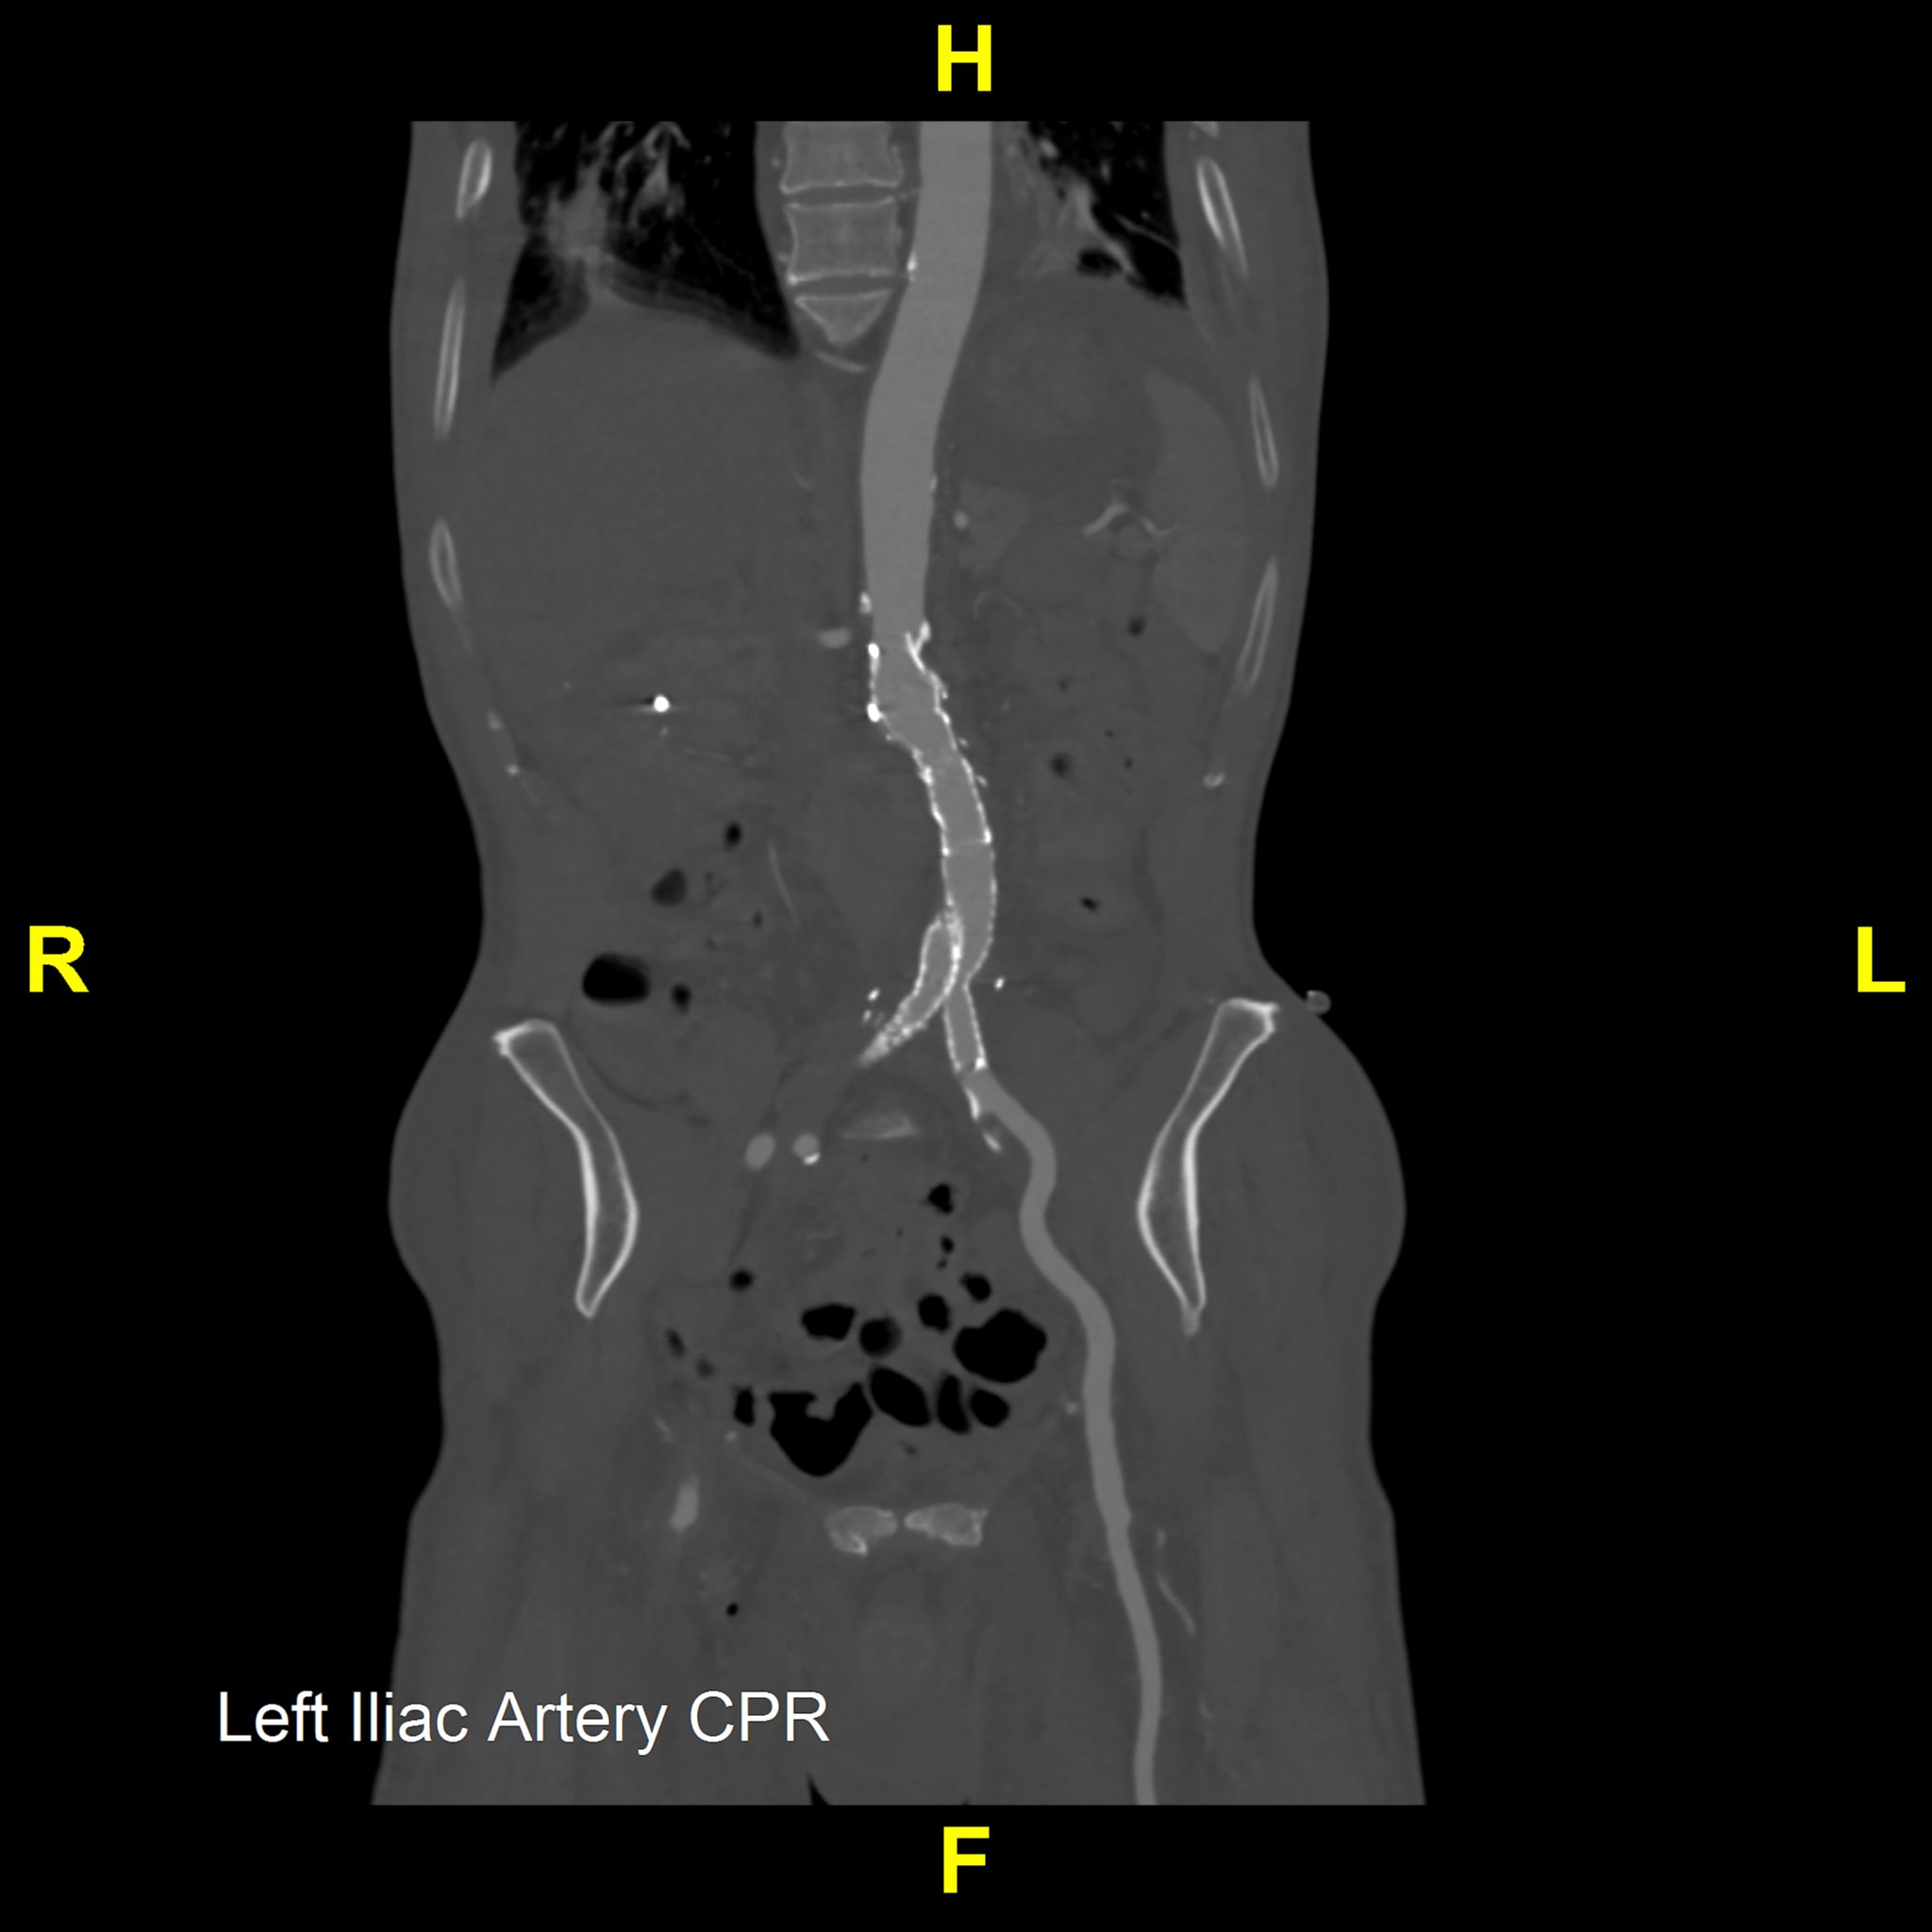

Our Post-Stent Service provides imaging for patients with stent placements in the abdominal aorta and common iliac arteries. The primary goal is to monitor changes in the maximum diameter of these vessels, ensuring early detection and management of post-stent issues. Using 3D imaging techniques identify critical aspects such as stent length, potential migration, and aortic diameter.

This protocol complements Routine Chest, Abdomen, and Pelvis imaging, offering an added layer of post-procedural monitoring. It allows quick viewing of major anatomy and focuses on identifying stent movement or aneurysm growth, ensuring comprehensive and effective monitoring.

Our Heart & Coronary Angiography service utilizes CT coronary angiography to assess the heart for hemodynamically significant calcific and soft plaques, as well as any anomalous anatomy, which may be useful for diagnosing and managing cardiovascular disease. We perform Curved Planar Reformation (CPR) on areas with minimal motion artifact, ensuring the clearest possible visualization of each coronary artery.

The service includes creating detailed CPRs for the Left Anterior Descending (LAD), Left Circumflex (LCX), Right Coronary Artery (RCA), and any bypass grafts, annotating native vessel names for understanding. We further enhance our evaluations with a 360-degree loop of each CPR providing an all-encompassing view of coronary anatomy.